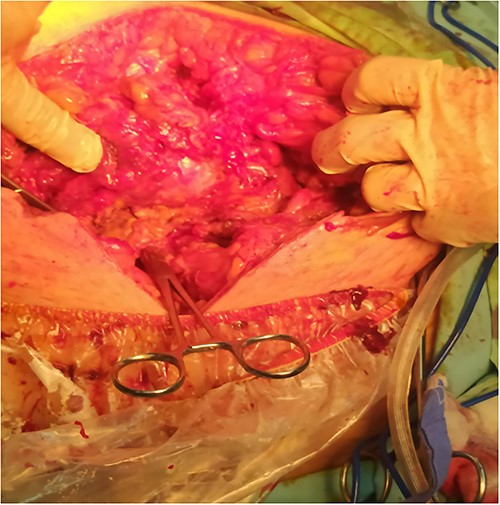

A 53-y-old morbidly obese female patient (BMI = 50) was diagnosed with colicky abdominal pain that progressively worsened over 1 week and became constant, without clear exacerbating or relieving factors. She also complained of fever, constipation, nausea, vomiting and anorexia. Past surgical history was significant for a surgically repaired umbilical hernia 10 y ago. The pain gradually became continuous and more severe, warranting hospital admission for further evaluation. On physical examination, the patient appeared unwell, dehydrated, and severely distressed. Vital signs showed a blood pressure of 100/60 mm Hg, pulse of 90 bpm and a temperature of 38 °C. Oxygen saturation was 95% on ambient air. Abdominal examination revealed midabdominal tenderness with mild abdominal distension, as well as high-pitched bowel sounds. Notably, there was an infected wound measuring 20 cm × 13 cm on the midline of the abdomen with signs of poor healing, tissue necrosis, and foul-smelling discharge (Fig. 1). Rectal examination was inconclusive. Laboratory tests indicated elevated levels of inflammatory markers, including a C-reactive protein (CRP) level of 445 mg/L and a white blood cell count of 30 000/ml. Hemoglobin level was 7.8 g/dl with a mean corpuscular volume (MCV) of 65. Additional abnormal results included a creatinine level of 1.8 mg/dl and a random blood sugar level of 310 mg/dL. Electrolyte levels were normal. Based on the laboratory findings, the LRINEC score was calculated to be 11, suggesting a high risk of NF. A plain abdominal X-ray showed fluid levels in the small intestine but no signs of pneumoperitoneum (Fig. 2). Abdominal ultrasound revealed localised swelling and fluid accumulation in the anterior abdominal wall, with dilated and edematous small intestine loops trapped within. The patient was ultimately diagnosed with strangulated incisional hernia complicated by NF of the abdomen. Management included nasogastric decompression, intravenous fluids and broad-spectrum antibiotics. Subsequently, the patient underwent emergency wound debridement under general anesthesia using a left paramedian laparotomy incision (Fig. 3). During the procedure, necrotic and dark skin, as well as friable subcutaneous tissue, were observed and resected (Figs 4 and 5). Approximately 500 ml of pus and digested food particles were drained from the abdominal wall. Controlled irrigation of the wound with saline was performed, and the strangulated bowel was identified, resected, and a loop ileostomy was created. There was no contamination of the peritoneal cavity. Two surgical drains were inserted, one in the abdominal wall and one in the peritoneal cavity. As the wound was considered contaminated, the fascia was sutured, but the skin edges were approximated and left open for secondary healing (Fig. 6). A temporary cover was applied using a plastic sheath (Fig. 7). The patient was then transferred to the intensive care unit (ICU) for continued postoperative wound care and debridement. On the 7th day, the patient was started on a soft diet and referred to the plastic surgery unit for ongoing wound treatment.

Surgical debridement and fasciotomy of the anterior abdominal wall.